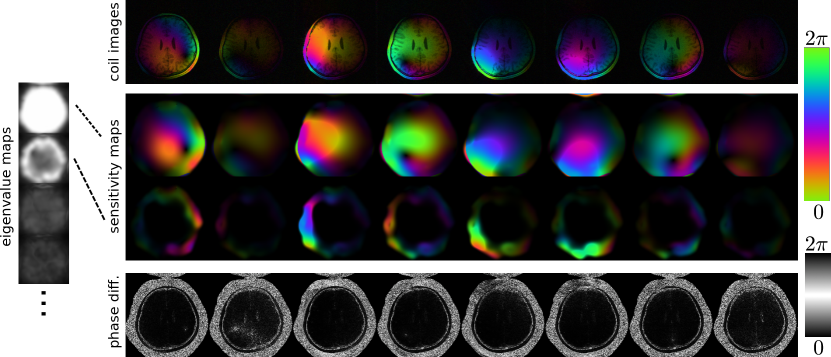

Figure 2: VCC-ESPIRiT was applied to a calibration region of size 24x24 of a human brain data set. Left: The first four from 64 eigenvalue maps from VCC-ESPIRiT calibration. In some regions a second eigenvalue close to one indicates the existence of a second set of maps. Right: Coil images, the first and second set of sensitivity (eigenvector) maps, and a phase-difference map between the coil images and the first set of maps are shown (only the first eight out of 32 physical channels are shown). Except for the phase-difference map the phase is encoded using color.

Figure 2 shows individual coil images and the first two sets of maps computed with VCC-ESPIRiT for the first eight channels of the brain data set. The primary set of maps represents the coil sensitivities with image phase which matches the phase of the coil images except for high-frequency phase components. A second set of maps appears in image regions affected by this high-frequency phase, which - in this example - is caused by off-resonance from fat.